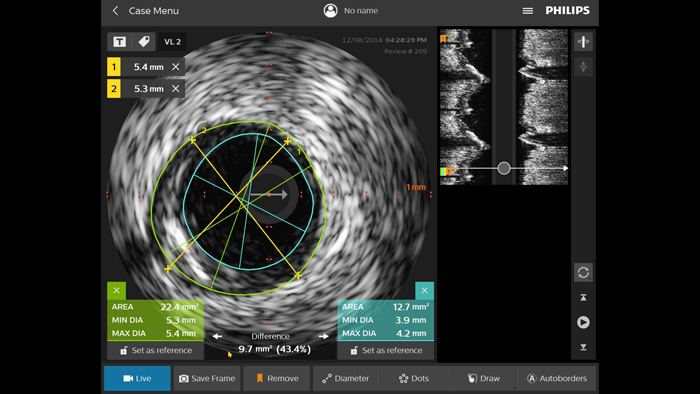

Optimice los resultados de los pacientes mediante un criterio estandarizado de IVUS. 1,2 En comparación con la PCI guiada por angiografía sola, en todos los pacientes, ULTIMATE muestra que la PCI guiada por IVUS reduce, de forma significativa, la revascularización de la lesión (TLR) impulsada clínicamente. Este beneficio se mantuvo durante tres años. Solo el 1,6 % de fallo en el vaso (TVF)* a los 12 meses y el 4,2 % de TVF a los 3 años cuando se cumplieron los criterios óptimos de la PCI guiada por IVUS.

El iFR es el principal índice fisiológico sin hiperemia para medir la presión en procedimientos de diagnóstico e intervención que es reconocido por las sociedades cardiovasculares clave4,5,6,7 Solo con el iFR se han validado clínicamente los datos de los resultados de los pacientes en los estudios de fisiología más grandes de la historia.1,2,3,9 El corregistro del iFR mapea las mediciones fisiológicas, directamente sobre el angiograma y permite una guía de procedimiento más completa.